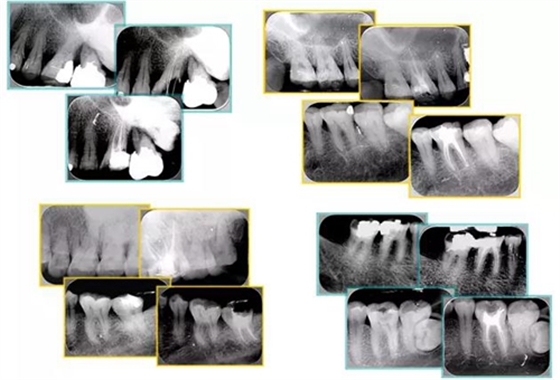

6. 術(shù)后 X 線(xiàn)片

術(shù)后 X 線(xiàn)片用來(lái)評(píng)定根管充填 長(zhǎng)度、致密度(管壁清晰、側(cè)枝)等指標(biāo)。

左圖為根管充填術(shù)后 X 線(xiàn)片。圖中可見(jiàn),根管充填較好。右下圖有白色小點(diǎn),為側(cè)方加壓導(dǎo)致糊劑擠出所致,表明根管充填比較致密。

致密、恰到好處的充填可去除干凈根管里感染灶,機(jī)體逐漸恢復(fù)。

多根牙時(shí)候需進(jìn)行偏移投照,正位投照無(wú)法說(shuō)明具體哪根牙根管充填效果。